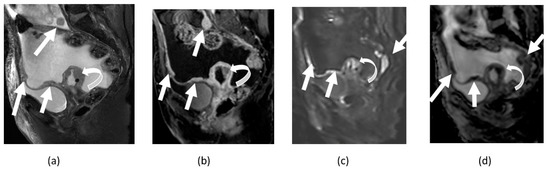

4.1. Cervical Cancer

4.2. Endometrial Cancer

4.3. Ovarian Cancer

5. Pitfalls of DWI